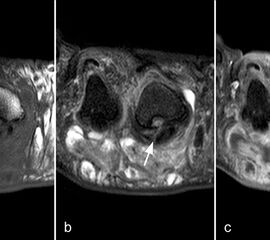

Der Begriff Morton-„Neurom“ ist im Grunde veraltet und irreführend, denn es handelt sich weder um einen Nerven- noch um einen Nervenscheidentumor, sondern um eine perineurale Fibrosierung. Da das interdigitale Gefäßnervenbündel charakteristisch in die Läsion hinein- und distal auch wieder aus der Läsion herauszieht, entsteht lediglich das Bild eines vom Nerven ausgehenden Tumors. Die charakteristischen Merkmale von Morton-„Neuromen“ sind deren Lage plantar auf Höhe der Metatarsaleköpfchen und die oft typische tropfenförmige Konfiguration (Abb. 10).

Aufgrund des hohen Bindegewebsanteils sind sie in der MRT in T2-gewichteten Bildern in der Regel auffallend signalarm, die T1 zeigt eine unspezifische Weichteilintensität. Die Anreicherung nach intravenöser Kontrastmittelgabe ist sehr variabel und erlaubt somit kaum diagnostische Rückschlüsse.

Durch seitliche Kompression des Fußes verlagern sich Morton-„Neurome“ oft weiter nach plantar in die Weichteile. Klinisch entspricht dies dem sogenannten Mulder-Zeichen 4. In der Bildgebung kann man sich den Effekt zu Nutzen machen, indem man in Bauchlage untersucht und durch die seitliche Fixierung eine entsprechende Kompression erzeugt. Die Befunde sind dann oft deutlich besser zu erkennen (Abb. 11).